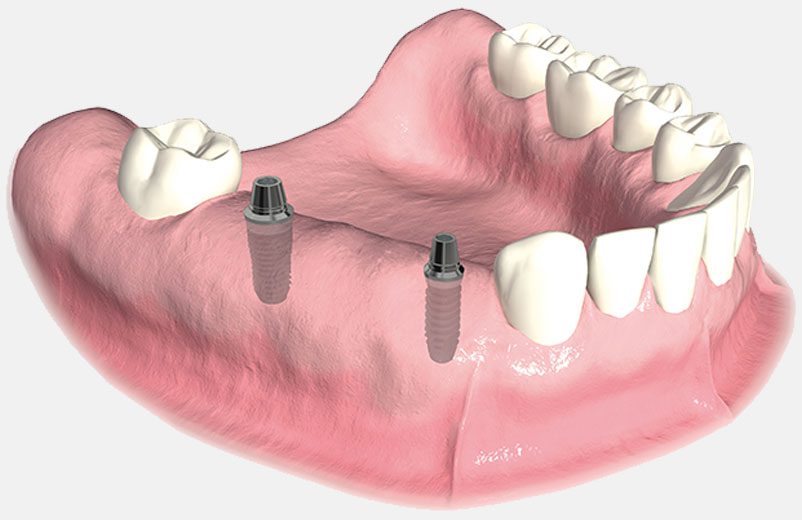

Á Prothese Stabilisee Sur Implants Refaites Vos Dents Au Meilleur Prix. Réponse du dr dupeyrat gérard stomatologue implantologue à paris 75008. Quels risques si le dentier n'est pas nettoyé assez souvent? Prothèse partielle supérieure uniquement à partir de prothèses flexibles à bas prix si vous avez au moins 6 dents naturelles dans votre mâchoire supérieure, achetez cette prothèse souple supérieure pour égayer votre sourire! Vous avez 14 jours � r�ception de votre d�guisement pour changer d'avis et nous le renvoyer gratuitement pour obtenir votre remboursement. Pour le dentiste, des cours dentaires de démonstration et d'enseignement. 1 prix d'un dentier 2 remboursement d'un dentier 3 dentier:peux t on le deviner? Fixer son dentier grâce aux implants dentaires: 1:54 62ltmformation 24 652 просмотра. 0 reviews add a review. Moulage prise d'empreinte à l'alginate & fabrication d'un dentier par coulée en plâtre. 4 avec un dentier,ma prononciation sera t elle changée? Retour gratuit sur le produit : Veuillez noter que vous devez dabord acheter le « kit dimpression complète. Notre coup de cœur dentier souple au mois de d'octobre 2020. 7:01 marc duquesnoy 106 543 просмотра.